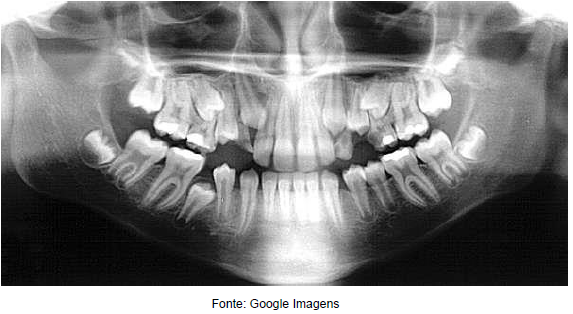

Observe a imagem abaixo mostra uma radiografia revelada através de um sistema digital. Assinale qual o tipo de radiografia representada.

Enunciado 743845-1